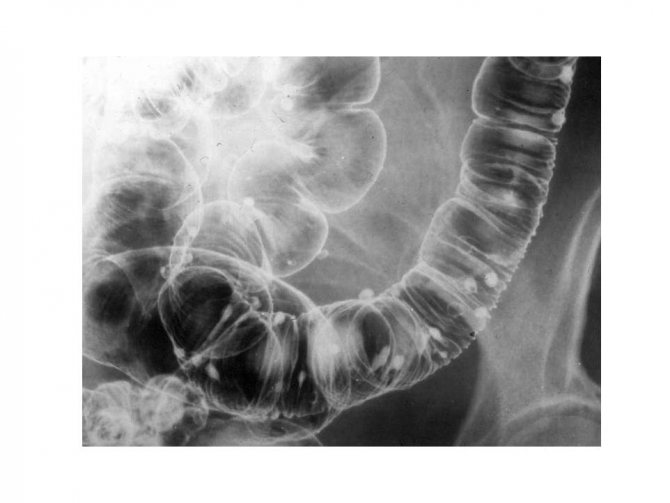

Чтобы вещество распределялось равномерно, больного просят переворачиваться. Проведение процедуры контролируется рядом снимков. После выведения контрастного вещества кишечник наполняют воздухом, чтобы расправить складки, и делают ещё несколько снимков. Двойное контрастирование позволяет рассмотреть новообразования и язвы, возможна диагностика рака толстой кишки.

В просвет толстого кишечника вводится ренгеноконтрастное вещество (чаще бариевая взвесь). После этого проводят серию рентгеновских снимков и анализируют полученный результат. Дополнительно в просвет кишечника может быть введён еще и воздух. Данный метод позволяет увидеть все отделы толстого кишечника, даже труднодоступные для колоноскопа.

Во время ирригоскопии доктор делает снимки толстой кишки, перед этим заполнив всю ее полость сульфатом бария. Этот раствор заполняет кишечник и позволяет рентгену лучше рассмотреть патологии кишечника. Если его не использовать и сделать снимок, то на нем вы ничего не увидите. Только по снимкам доктор может поставить диагноз.